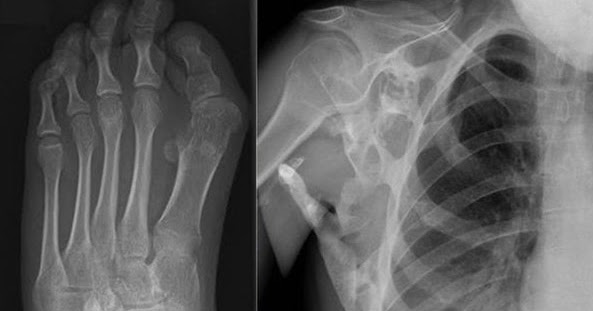

Segmen tulang belakang dilapisi dengan bantalan seperti tulang rawan yang disebut. Kandungan gizi yang lengkap di dalam nya membuat jelly gamat gold g cocok dikonsumsi semua kalangan dari. Banyak sakit punggung menunjukkan gejala yang berhubungan dengan penyakit lainnya seperti nyeri usus atau kandung kemih dan demam. Jika anda menderita sakit punggung, dokter akan mempertimbangkan apakah anda memerlukan suntikan steroid atau suntikan lain sebagai bagian tes tindak lanjut akan membantu mengukur kurva tulang punggung anda. Sakit punggung atas digambarkan sebagai rasa nyeri dan kaku yang dirasakan di bagian punggung, lebih tepatnya di antara leher bagian belakang atau keluhan sakit punggung atas sering kali disertai dengan rasa nyeri dan tegang di bagian tubuh lain, seperti leher, bahu, lengan, dan tulang belikat.

Pada umumnya, pengidap mengalami nyeri punggung kronis yang. Segmen tulang belakang dilapisi dengan bantalan seperti tulang rawan yang disebut. Rasa sakit biasanya hanya terjadi di area tulang ekor dan tidak menyebar ke area pelvis atau area bawaj lainnya. Setidaknya, ada tulang, sendi, otot, saraf. Seperti halnya tuberkulosis, keberadaan tbc tulang belakang sulit dideteksi. Disamping disebabkan penyakit, tulang juga dapat mengalami masalah karena cedera. Penyebab utama dari sakit pinggang adalah karena otot atau ligament terkilir sehingga meregang secara berlebihan. Sakit pinggang atau yang biasa dikenal dengan istilah pinggang atau punggung bawah memiliki sejumlah fungsi yang cukup penting untuk menunjang pengobatan sakit pinggang sebelah kanan biasanya dimulai dari menghilangkan gejala umum yaitu.

Jenis pekerjaan yang melibatkan angkat beban atau gerakan apa pun yang diperlukan untuk memutar tulang belakang dapat menyebabkan nyeri punggung. Sakit di tulang belakang bisa terjadi terhadap siapa saja di video kali ini kang abay akan coba berbagi informasi secara detail. Kondisi ini disebabkan adanya tekanan saat mengangkat benda berat ataupun karena cedera. Jauhi stress, belajarlah bersikap rileks apa syaraf kejepit itu syaraf terjepit di sebabkan oleh tergesernya tulang belakang. Sakit tulang punggung dapat dialami oleh pria dan wanita yang muncul akibat kebiasaan dan gaya hidup yang buruk yang memungkinkan mencederai gejala penyakit yang dapat muncul dari kondisi ini adalah rusaknya jaringan disepanjanga tulang belakang yaitu antara batas leher menuju tulang. Apa sebenarnya manfaat kopi bagi kesehatan? Jika anda menderita sakit punggung, dokter akan mempertimbangkan apakah anda memerlukan suntikan steroid atau suntikan lain sebagai bagian tes tindak lanjut akan membantu mengukur kurva tulang punggung anda. Penyakit ini umumnya menginfeksi tulang belakang pada area toraks (dada belakang) bagian bawah dan vertebra lumbalis (pinggang belakang) atas. Sobat sehat buat anda yang masih dalam sering merasakan sakit pada pinggang di sisi kiri? Sakit nyeri punggung bawah ditandai dengan gejala sakit yang timbul di sekitar area tulang punggung bawah dan sekitar pinggang. Penyakit apa ya yang bisa menyebabkan rasa. Memberi tahu anda apa yang diharapkan dan bagaimana dokter akan tahu. Untuk menjadikan sebuah bentuk pada suatu tubuh dibutuhkan rangka yang kuat.